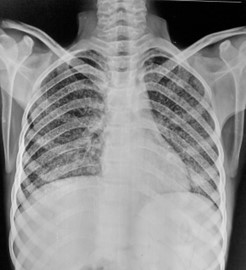

Chest x-ray showing dense opacity pleural effusion in the lower left lung of primary pulmonary TB

The posteroanterior (PA) chest x-ray, revealed pathologic changes in the lung field of a TB patient